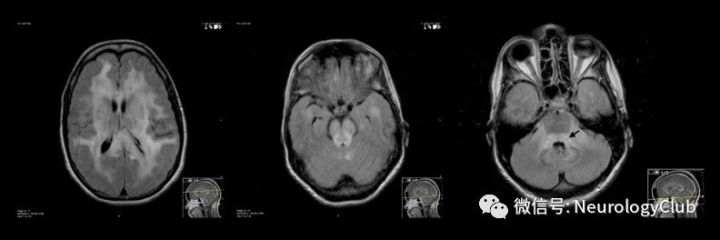

神经白塞病包括实质型和非实质型。实质型神经白塞病约占70-80%,病灶以脑干(脑桥、中脑)常见,也可延伸累及间脑、基底节区。累及大脑半球时,常为多发的小白质病变,也可表现为孤立性类瘤样病灶。脊髓受累时可见单发或多发的不同长度的炎性病变,常位于颈胸髓。也可有脑膜脑炎,表现为脑膜强化。急性期病灶在T1WI上呈等-低信号,增强通常为片状强化,也可出现环形强化,T2WI和FLAIR上为高信号,DWI上高信号,相应ADC值降低。部分病灶中心或周围可见出血。累及脊髓时横断面T2WI可见“百吉饼(在美国纽约较为流行,也称硬面包圈)征(Bagel Sign)”。慢性期,病灶多缩小,通常无强化,可见脑萎缩,尤其是脑干。

(图29:长节段脊髓受累的NBD患者T2WI横断面可见“百吉饼征”,或与静脉怒张有关,可能为其特征性影像,有助于与其他长节段脊髓病变,如视神经脊髓炎谱系疾病等鉴别

鉴别诊断